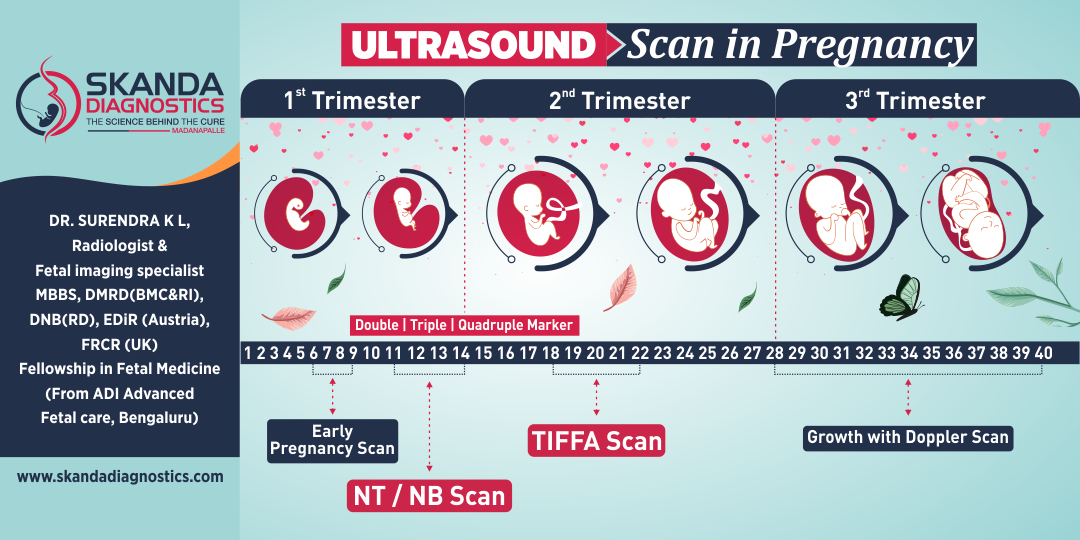

Skanda Advanced Ultrasound Scan Centre starts right from the onset of pregnancy. Our Fetal Medicine experts are concerned with the health of the fetus at every stage – monitoring growth & development; predicting, detecting & managing any complications; and treating congenital disorders & anomalies in the womb itself.

Skanda Advanced Ultrasound Scan Centre starts right from the onset of pregnancy. Our Fetal Medicine experts are concerned with the health of the fetus at every stage – monitoring growth